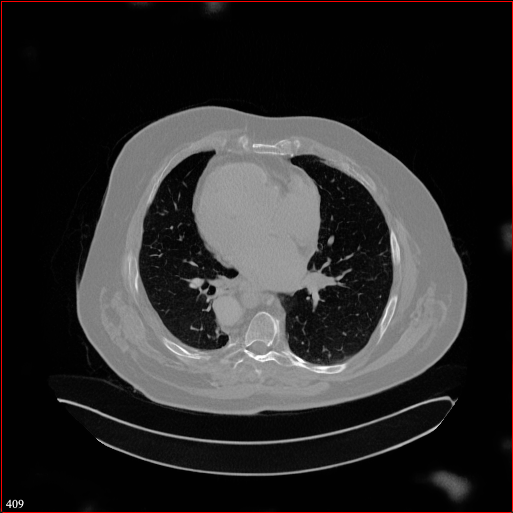

Figure 2: Qualitative comparison across axial (top row), sagittal (middle row), and coronal (bottom row) views. Columns correspond to different methods. MAISI-DDPM and MAISI-v2 in this figure are unconditional synthesis which do not use ControlNet or segmentation maps.

Qualitative Evaluation:

Figure 2 presents representative slices from the axial, sagittal, and coronal planes. GenerateCT (hamamci2024generatect) is a 2D model, so it lacks inter-slice consistency, leading to poor image quality in the sagittal and coronal views. MedSyn (xu2024medsyn) produces noticeably blurry results with mosaic-like artifacts, such as region inside the red box. HA-GAN (sun2022hierarchical) generates visually sharp images but with mosaic-like artifacts, such as region inside the red box. Also, its voxel spacing is not available, which limits its applicability in real-world medical imaging tasks. Moreover, all three methods are restricted to synthesizing small anatomical regions. In contrast, both MAISI and MAISI-v2 are capable of generating high-quality 3D volumes that span larger body regions while preserving fine anatomical details and realistic structure.